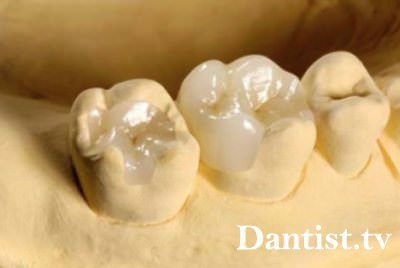

Inlay kerámiából készült, és pontosabban az orvosi porcelán. Tökéletesen szaporodik a természetes fogzománc. A fogtechnikus tehet egy protézis, hogy nem valószínű, hogy valaki megkülönböztetni. És az árnyék és homály, és a forma és a természetes tompítása - az összes akkor meg tökéletes.

Úgy tartják, hogy a porcelán - ez egy nagyon törékeny anyag. De valójában nem az, ha egy meglehetősen vastag kerámia erőt, hogy össze lehet hasonlítani még a fogzománcot. Ezért fogorvosok kétségtelenül használja ezt az anyagot a helyreállítás őrlőfogak.